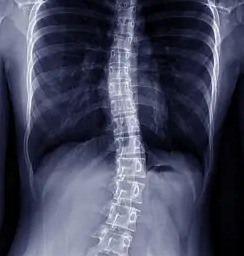

Scoliosis is a deformation that affects the spine. Most common in adolescents, scoliosis causes the spine to curve from side to side, creating a C or S shape. In severe cases, the curves can be greater than 45 degrees. Curves like this are extreme, but fortunately, they are easily correctable with scoliosis surgery.